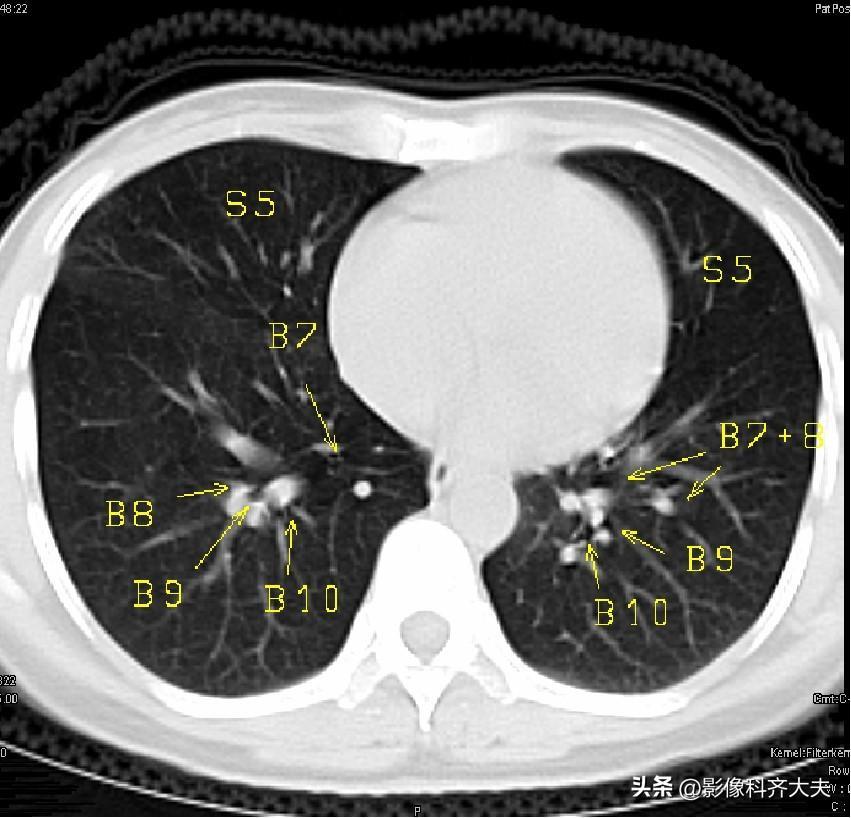

图16-近心底层面

▲B7:下叶内段支气管,B8:下叶前段支气管,B9:下叶外段支气管,B10:下叶后段支气管